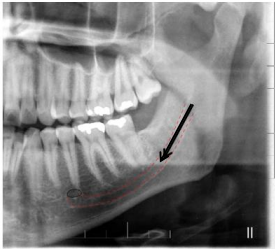

Considerando a radiografia panorâmica apresentada, a estrutura anatômica indicada pela seta e pelo tracejado corresponde a:

A radiografia panorâmica é a técnica extrabucal

mais solicitada em odontologia. Entre as suas

indicações estão a visão ampla do complexo

maxilomandibular, a avaliação da relação entre

dentes decíduos e permanentes, o

posicionamento de terceiros molares

inclusos/impactados, o estudo de anomalias

dentárias, a extensão de lesões patológicas e

alterações metabólicas, além do diagnóstico de

fraturas mandibulares e da ATM.